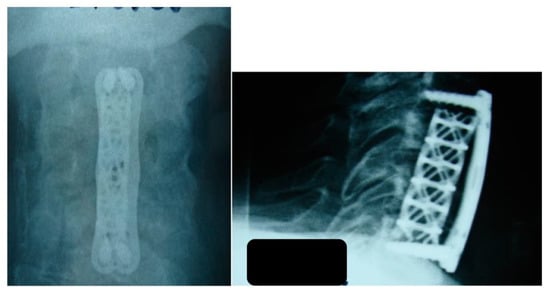

| 1 | 23 | M | C2–C4 | Staphylococcus aureus | Debridement and fusion | Fever, pain, numbness, and muscle weakness bilaterally | Full recovery, dysphagia for 2 weeks postop | Abuse of venous drugs |

| 2 | 68 | M | C2–C4 | Staphylococcus aureus | Debridement and fusion | Fever, pain, numbness, and muscle weakness bilaterally | Full recovery | Diabetes mellitus |

| 3 | 56 | F | C1–C5 | Staphylococcus aureus | Debridement and fusion | Fever, pain, numbness, and muscle weakness bilaterally | Full recovery 2 years post op, muscle weakness | |

| 4 | 69 | M | C2–C5 | Staphylococcus aureus | Debridement and fusion | Incidentally upon spinal imaging | Full recovery, dysphagia for 2 weeks postop |